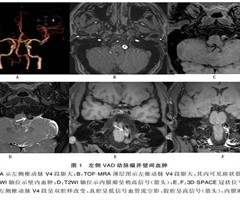

高分辨率磁共振血管壁成像对椎动脉夹层的诊断价值

摘要目的:探讨高分辨率磁共振血管壁成像(HRMR-VWI)在椎动脉夹层诊断中的应用价值。方法:搜集2例经临床证实为椎动脉夹层病人的临床及影像资料,均获取磁共振时间飞跃法磁共振血管成像(TOF-MRA)、快速自旋回波T1加权成像(T1WI)、...